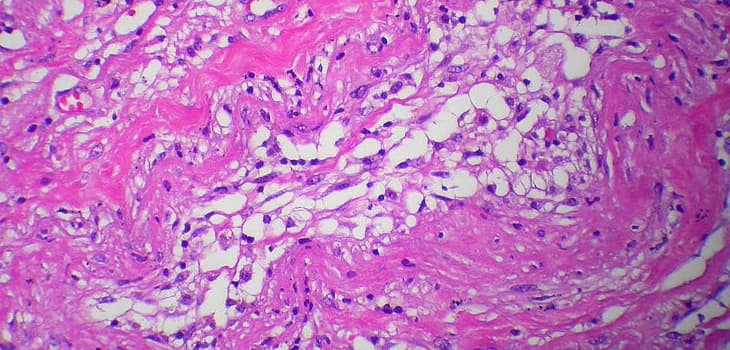

Lipogems® pour le traitement de l'atrophie urogénitale - AICPE 2018

Une étude clinique menée par le Prof. Carlo Tremolada et le Dr G. A. Casarotti sur le traitement de l'atrophie urogénitale par la méthode Lipogems® a été...